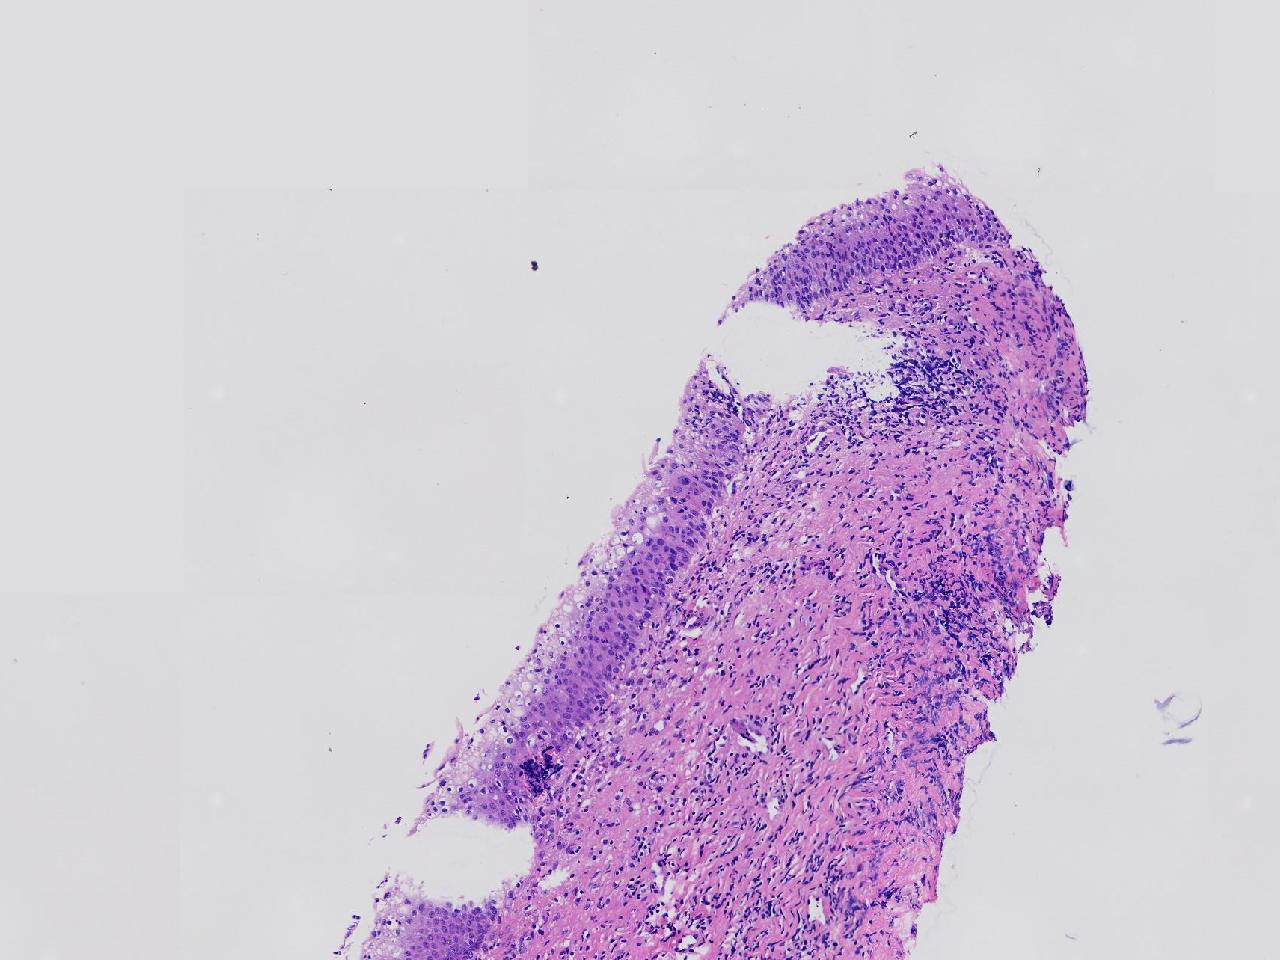

女,59岁,宫颈活检,TCT报告ASC—US, HPV不详。

宫颈多点活检。

灰白色不整形软组织多块。

CIN1,建议HPV检测

高级别